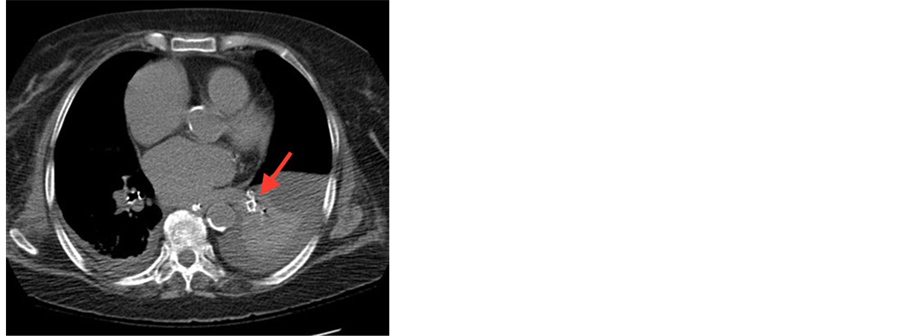

Flexible Bronchoscope showed no bronchial lesions. Alveolar lavage with multiple consecutive aliquots of 50 ml of Normal saline was performed. Bloodier returns were documented among lavage tubes. Microscopic exam shows 50% Hemosidrinladened macrophages. Chest CT scan without contrast showed grains of Cement in the pulmonary parenchyma particularly in the left lower lobe (Figure 3). In addition, there was a two grams drop in the hemoglobin (from 9 to 7 g/dl). The diagnosis of diffuse alveolar

Figure 3. CT chest without contrast. Grains of Cement in the pulmonary parenchyma at the left lower lobe. See red arrow.